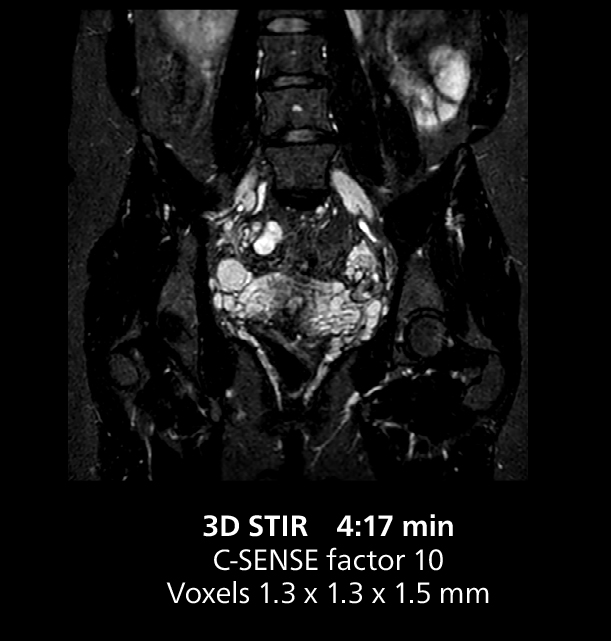

Dr. Gellée highlights the robust free-breathing scans as “the feature that makes the biggest difference in my daily work. The 3D free breathing sequences are very reproducible, and the axial acquisition is very good. For example, in endometriosis, which is one of my focus areas, it provides high contrast and good resolution so that I can see small details. We also use free breathing for liver and pancreas imaging. In multi-phase liver studies, 4D Free Breathing delivers 3-second temporal resolution, making a dynamic scan with more than one arterial phase possible.”

This MRI case illustrates good resolution and imaging quality obtained within reasonable scan times using the MR 5300 1.5T system with the anterior torso cardiac coil that allows use of a large field of view (FOV).